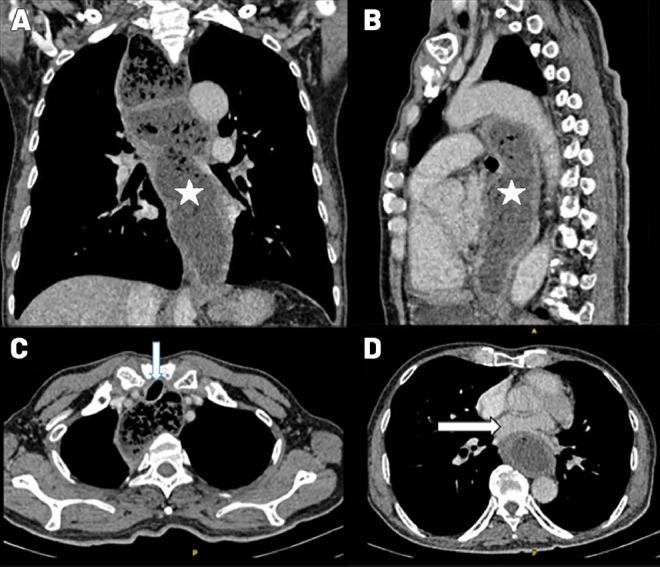

Achalasia is an uncommon disorder affecting esophageal motility. Occasionally, the appearance of a dilated esophagus in achalasia may resemble an extracardiac tumor when observed through transthoracic echocardiography. Left atrial compression due to extensive esophageal dilation is also rare, potentially leading to hemodynamic compromise. Here, we present a rare case involving left atrial compression caused by esophageal dilation in achalasia, with echocardiographic findings mimicking those of an extracardiac tumor.

贲门失弛缓症是一种影响食管动力的罕见疾病。偶尔,通过经胸超声心动图观察时,贲门失弛缓症中扩张的食管外观可能类似于心外肿瘤。由于广泛的食管扩张导致左心房受压也很罕见,可能会导致血流动力学损害。在此,我们报告一例罕见病例,即贲门失弛缓症中食管扩张引起左心房受压,其超声心动图表现类似于心外肿瘤。